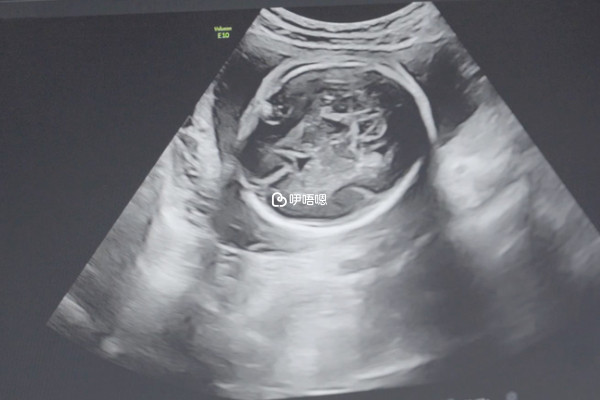

孕8周去醫院做B超檢查醫生說胎停了,就真的沒有希望了。因為胎停是指胚胎停止發育,也就是死亡,這種情況是沒有辦法挽救的,需及時在醫生的指導下進行處理,避免死胎在女性宮腔內停留時間較長,引起凝血功能障礙,對女性的生命健康造成影響。因此,當出現胎停時,女性也不要過於傷心,積極配合醫生處理,查明胎停原因,並做針對性治療,儘可能減少胎停的發生。

總之,孕8周確診胎停後,就沒有保胎希望了,要儘快在醫生指導下將胎兒以及附屬物排出體內。因為死胎長期殘留在子宮裡的話,可能會引起宮內感染,損害子宮內膜,進而導致輸卵管閉塞而不孕。所以建議各位孕媽在胎停後一定要保持一個良好的心態也為下次備孕做準備,沒有必要一開始就盲目保胎。